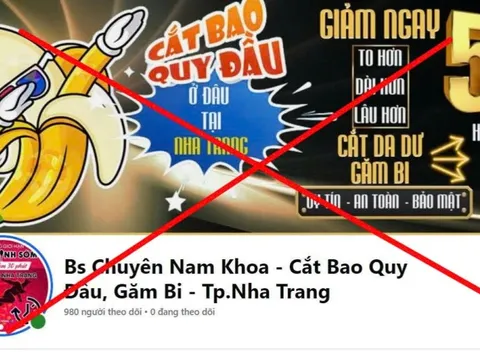

Nở rộ phòng khám 'chui', quảng cáo vi phạm ở Khánh Hòa

Nhiều cơ sở khám chữa bệnh tư nhân tại Khánh Hòa đang bị kiểm tra, xử lý do quảng cáo vượt phạm vi chuyên môn, thậm chí chưa được cấp phép hoạt động nhưng vẫn rầm rộ quảng bá dịch vụ trên mạng xã hội.